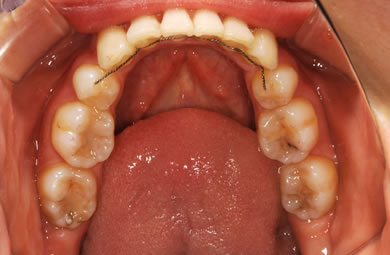

| 治療方針 | 口元が出ていていること、がたつきが大きいことより、上下左右の第一小臼歯および親知らずを抜歯し、マルチブラケット治療を行う。抜歯した隙間を活用できるよう上顎にはインプラントアンカー(釘)を使用し、その釘より歯を後ろに移動する。 | ||||||||||||||||||||||||||||||||

| 治療内容 | 唇側矯正(シルバー)、矯正用スピードインプラント、ハイブリッドセラミックインレー2本 | ||||||||||||||||||||||||||||||||